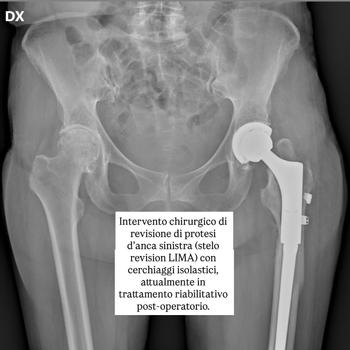

Fisioterapista con esperienza in riabilitazione ortopedica, neurologica, muscoloscheletrica, sportiva. Trattamenti domiciliari a Roma, basati su valutazione clinica accurata e programmi personalizzati.